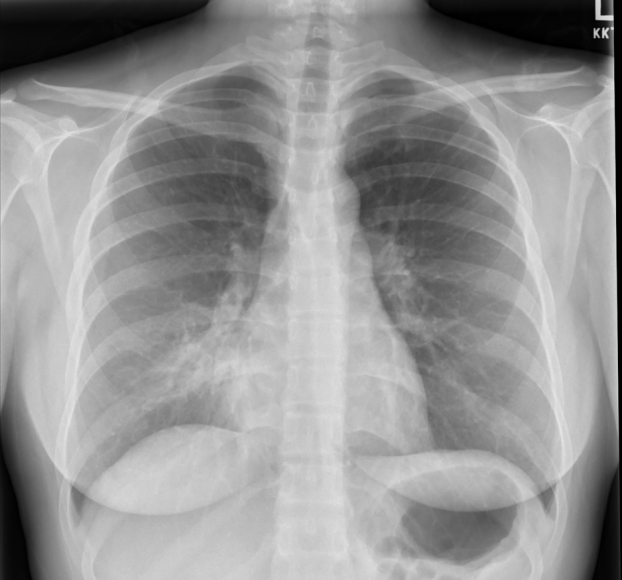

AP projection is obtained with the patient in bed and lying flat or partly upright. It is usually reserved for non-ambulatory patients. AP projections have the disadvantage of making the heart an mediastinum appear more prominent as well as usually resulting in shallower inspiration which can limit evaluation of the lung bases. A lateral projection is not obtained with a AP projection, thereby limiting the view of the chest further.

AP Projection – Widened Mediastinum and Less Inspiratory Effort

It is therefore preferable to order a PA/lateral CXR over an AP view when possible.